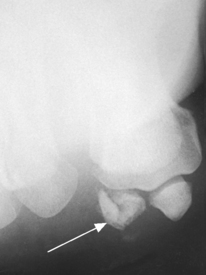

The five metatarsals are numbered one to five beginning at the medial or great toe side of the foot. The metatarsals consist of a body and two articular ends. The expanded proximal end is called the base, and the small, rounded distal end is termed the head. The five heads form the “ball” of the foot. The first metatarsal is the shortest and thickest. The second metatarsal is the longest. The base of the fifth metatarsal contains a prominent tuberosity, which is a common site of fractures.

| Jones | Avulsion fracture of the base of the fifth metatarsal |